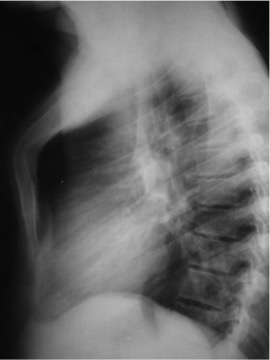

CASO: cáncer de mama. Control anual.

Hallazgos:

- Se observa un aumento de densidad con agrupación broncovascular que produce un borramiento del borde cardicaco derecho; hallazogos compatibles con atelectasia en el lóbulo medio. Véase el TC a continuación: